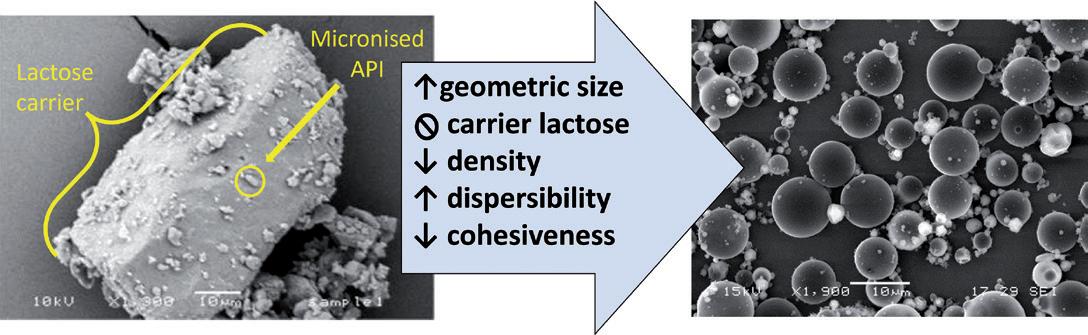

High-Dose Delivery Platform for Crystalline DPIs

Susana Saldanha, R&D Manager – Inhalation and Advanced Drug Delivery; Lídia Santos, Analytical Scientist – R&D ; and Rui Churro, Senior Scientist – Inhalation and Advanced Drug Delivery

Hovione